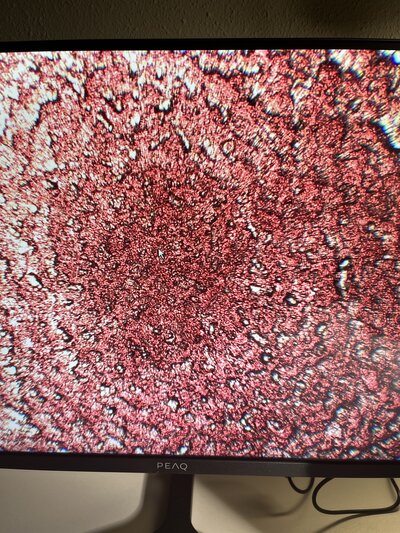

Met slechts één druppel bloed kijken we naar jouw eigen unieke bloed-universum. Live te bezichtigen onder de microscoop terwijl het nog leeft. Een klein beetje bloed, maar een wereld aan informatie! We kijken niet naar bloedwaarden, maar naar hoe jouw bloed zich gedraagt en daar kunnen we heel veel informatie uit halen.

Bij levend bloed bekijken we jouw bloed onder de microscoop terwijl het nog leeft! Ik neem je stapje voor stapje mee in wat we zien en wat het mogelijk vertelt over jouw lichaam. Een klassieke/reguliere bloedtest kijkt vooral naar cijfers/waarden en bij Levend Bloed Analyse (LBA) bekijken we juist hoe jouw bloedcellen samenwerken, bewegen en functioneren. Ook kijken we naar de kwaliteit, het plasma, de beweging en de vorm. Zo krijgen we een beeld van je immuunsysteem, verteringsprocessen en eventuele stresssignalen in je lichaam.

Nadat we jouw levende bloed hebben bekeken, bekijken we dezelfde druppel bloed opgedroogd. Dit geeft weer een heel ander landschap aan informatie.